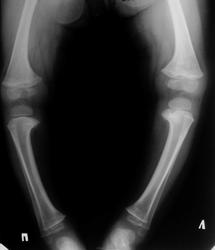

Искривление голеней имеет штыкообразный вид и определяется сразу же под коленным суставом. Вершина искривления обращена кнаружи. На уровне верхнего метафиза большеберцовой кости у всех больных определяется клювовидный выступ. Рано появляется выстояние головки мало-берцовой кости. Диафизы обеих костей голени всегда остаются прямыми. Обязательным и постоянным симптомом заболевания является внутренняя ротация голеней и часто рекурвация. Степень внутренней ротации может колебаться от 20 до 85°. По величине варусного искривления деформации голени могут быть разделены на три степени. К заболеваниям легкой степени относятся искривления во фронтальной плоскости с углом вируса от 5 до 13>, межмыщелковым расстоянием в 2-5 см. При заболевании средней степени величина угла вируса составляет 15-30°, а межмыщелковое расстояние равно 10-12 см. Тяжелые степени деформации характеризуются варусным углом от 30 до 55° и межмыщелковым расстоянием до 19-21 т. Из сопутствующих изменений при болезни Эрлахера-Блаунта выявляются понижение тонуса и атрофия мыши голеней. Почти у всех пациентов отмечается плоскостопие. Вил больных характерен (рис. 56). Они низкорослы из-за потери анатомической длины больше-берцовых костей, с более или менее выраженной варусной деформацией ног. Поэтому диагностика заболевания несложна. Рентгенологическая картина болезни Эрлахера-Блаунта довольно типична и представлена следующими признаками. 1. Отмечается искривление большеберцовой кости на уровне проксимального отдела метафиза, часто вблизи границы с эпифизом, что определяется в виде клювовидного костного выступа. 2. Деформация эпифиза - постоянный рентгенологический признак заболевания. Во всех случаях внутренняя часть суставной поверхности его располагается косо под углом 30-45° в дистальном направлении; она всегда деформирована - равномерно вогнута, нередко повышенно минерализована. Внутренний отдел эпифиза часто уменьшен по высоте почти в 2-3 раза. Возможна краевая фрагментация. 3. Как правило, с внутренней стороны сустава расширяется эпифизарная ростковая зона в виде раструба кости. Костно-замыкательные пластинки здесь нечеткие, расплывчатые. В последующем отмечается преждевременное закрытие хрящевых метафизарных зон роста. 4. Наблюдается компенсаторное утолщение кортикального слоя больше-берцовой кости по внутренней поверхности, с усилением внутрикостного рисунка. 5. Изменяется положение малоберцовой кости (наслаивается на больше-берцовую кость) из-за торсии голени.

Рахит. Болезнь Блаунта - поражение изолированное, а здесь варусная еформация голеней и бедер.